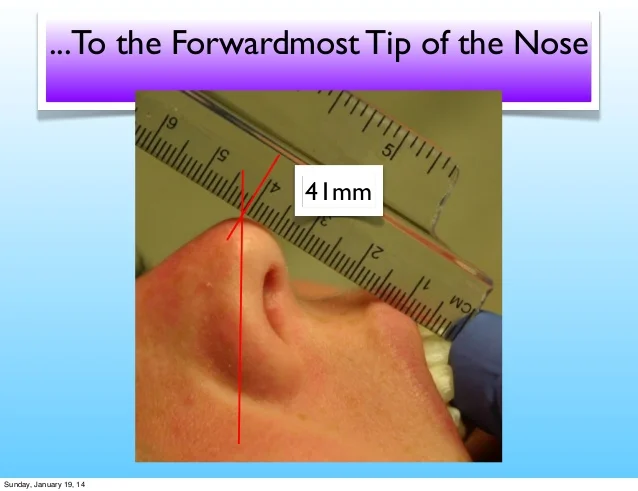

This kinda reminds me of the mew indicator line, indicator cheek line and what'd he go about evaluating SN line, FN plane and Cranial base angles

View attachment 4063414View attachment 4063415

It’s an approximation

This kinda reminds me of the mew indicator line, indicator cheek line and what'd he go about evaluating SN line, FN plane and Cranial base angles

View attachment 4063432View attachment 4063433View attachment 4063434View attachment 4063436View attachment 4063438View attachment 4063439View attachment 4063440